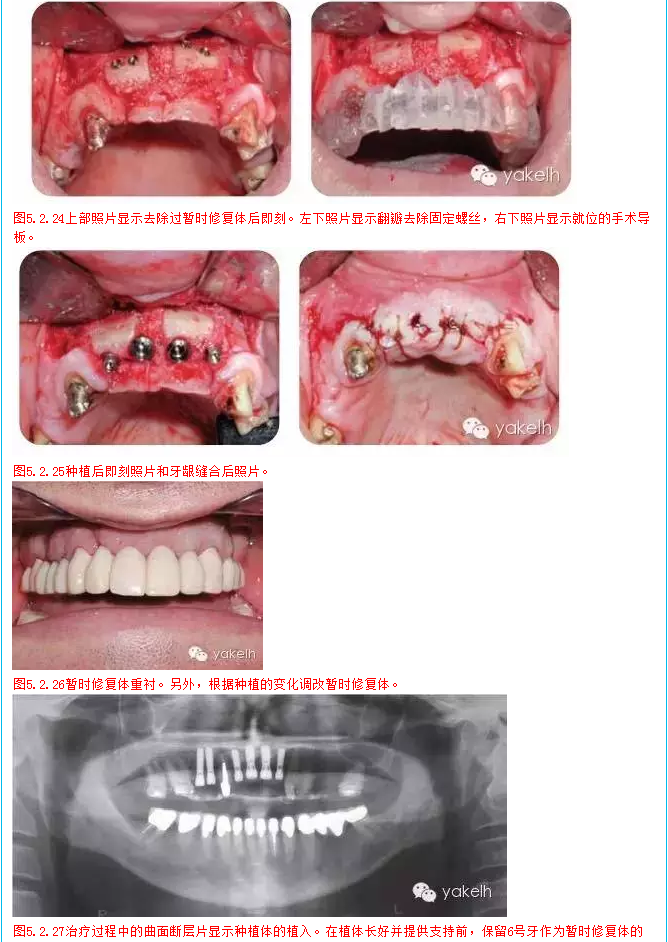

1  在2天內(nèi)分2次全牙列暫時(shí)性修復(fù)

2  種植區(qū)口腔外科骨移植手術(shù)

3  調(diào)整和修改暫時(shí)修復(fù)體

4  牙髓治療和牙髓再治療

5  完成下頜牙治療

6  4,5,7,8,9,10號(hào)牙種植修復(fù),6號(hào)牙仍作為暫時(shí)修復(fù)體的基牙

7  待種植后愈合和骨整合,調(diào)整和維護(hù)暫時(shí)修復(fù)體

8  安置種植體基臺(tái),拔除6號(hào)牙,制作種植體支持式暫時(shí)修復(fù)體

9  拔牙創(chuàng)愈合

10  最終的上頜修復(fù)體,2,3號(hào)牙為單獨(dú)修復(fù),4號(hào)至10號(hào)牙為種植固定橋,6號(hào)牙為橋體,11號(hào)至15號(hào)牙為牙支持式固定橋